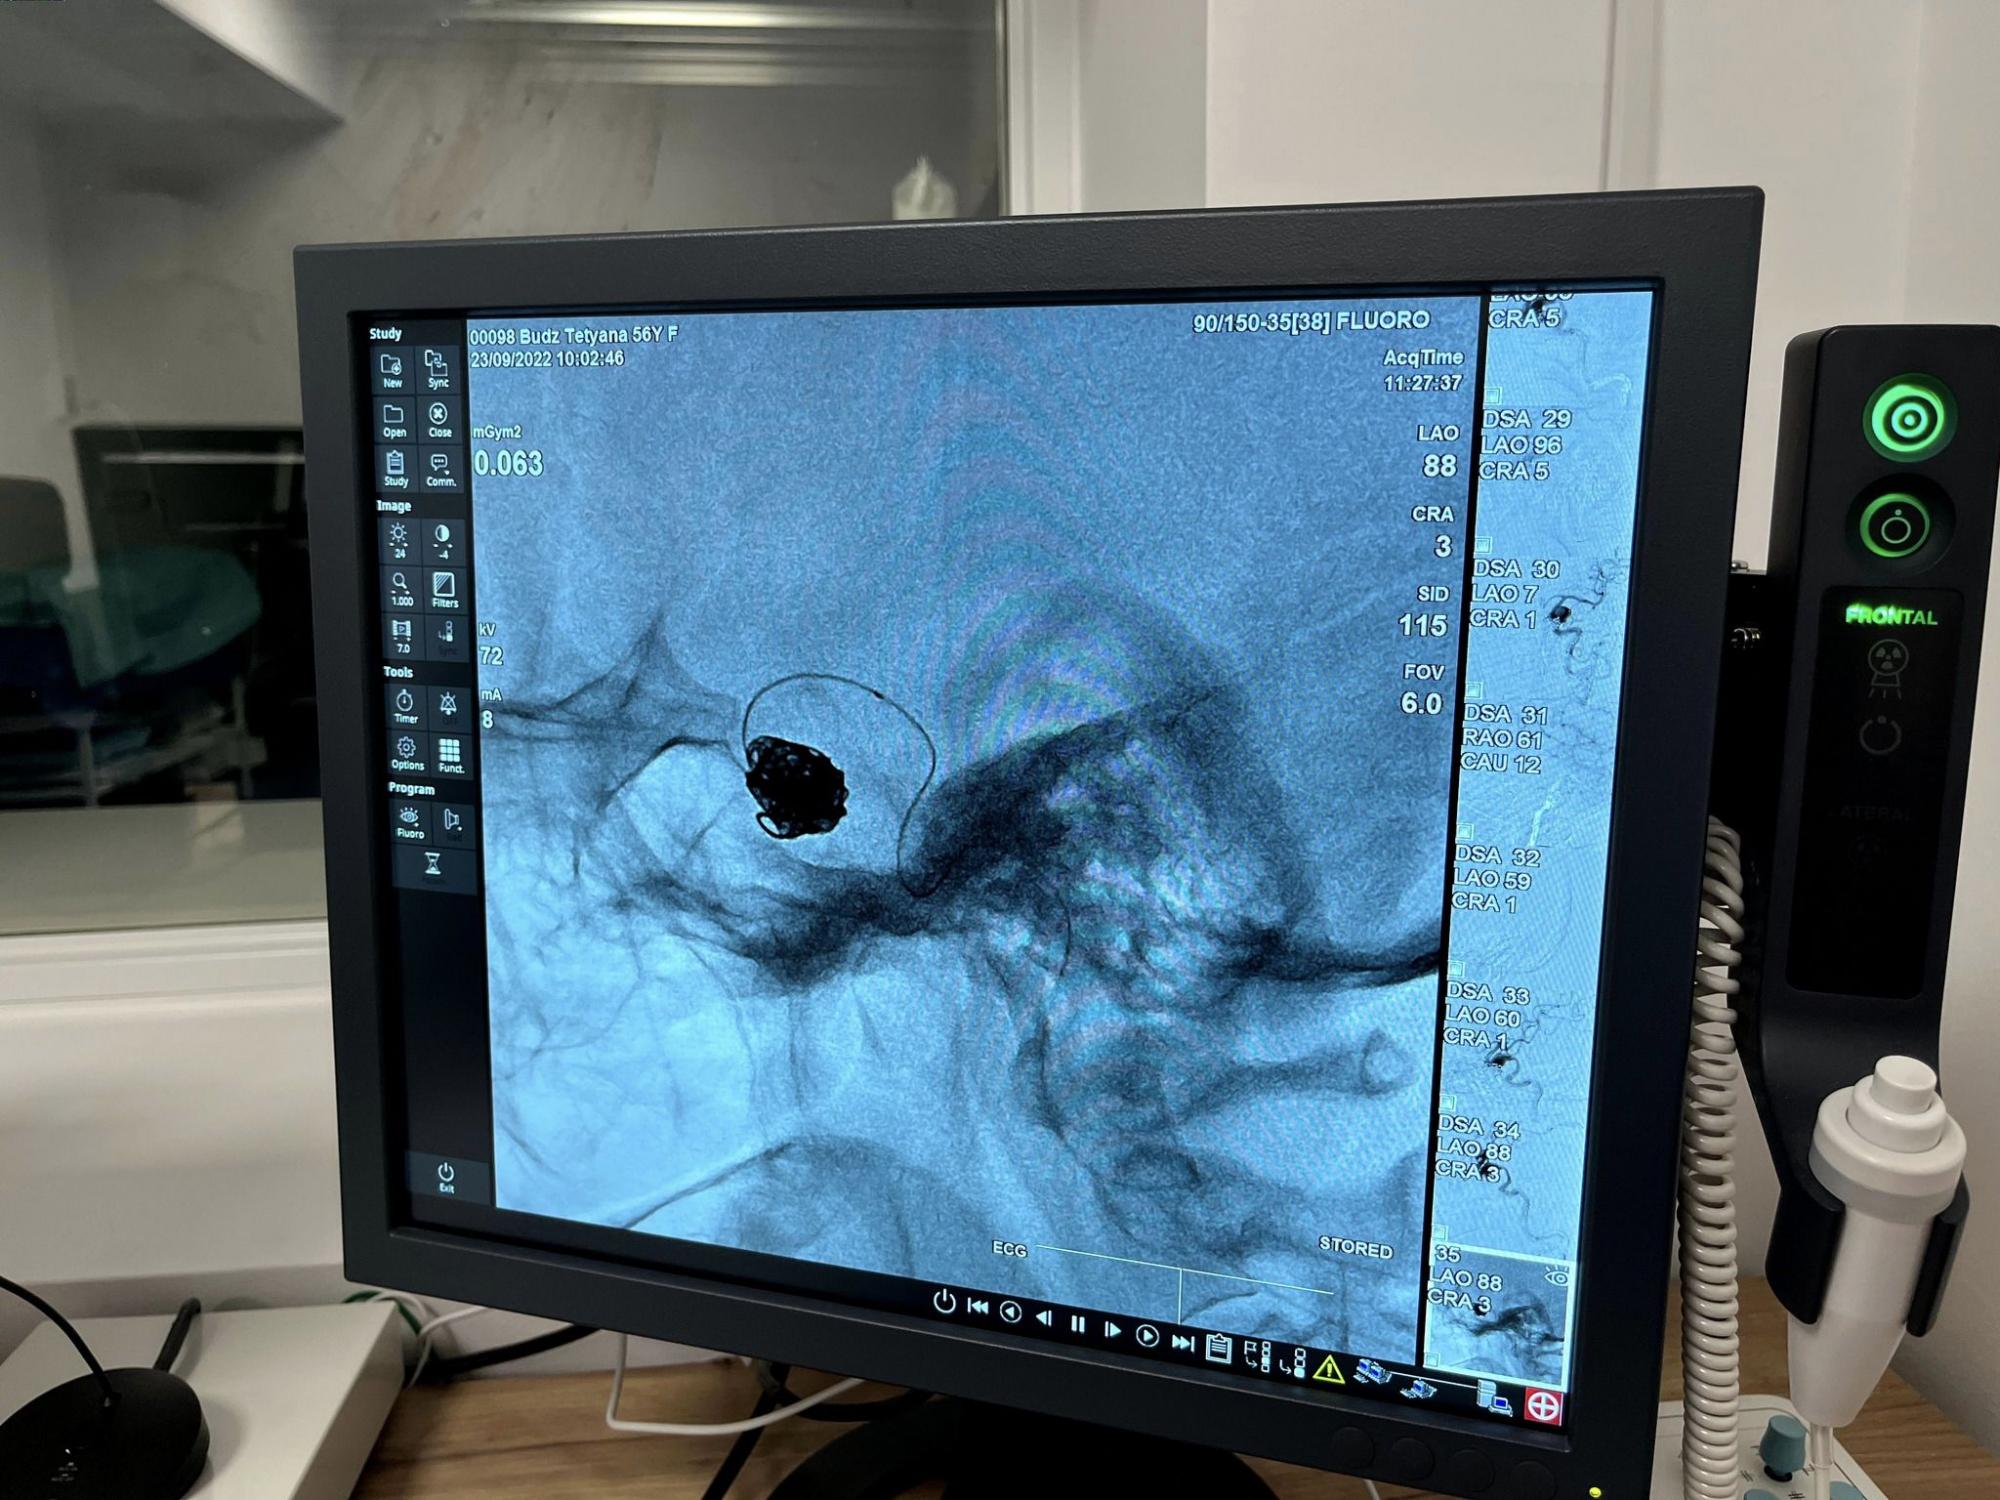

Фахівці лікарні Святого Луки Першого медичного об’єднання Львова врятували життя 56-річної пацієнтки, яку госпіталізували з величезною аневризмою головного мозку розміром півтора сантиметра.

За їхніми словами, після діагностики жінці повідомили, що у неї велика аневризма мозкової артерії. І вже наступного дня фахівці відділення реперфузійної терапії та радіології виконали емболізацію - закриття аневризми за допомогою мозкових спіралей.

Зазначається, що операція відбулася без розрізів - тільки одним проколом завдовжки до 5 мм.